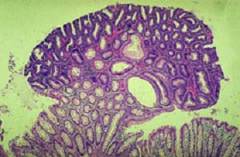

Слизистая оболочка желчного пузыря образует множество складок и выстлана однослойным эпителием с железами.

Причины возникновения полипа

Прежде чем рассматривать причины появления полипов, важно знать их виды. Существует два основных типа: истинные и псевдополипы. Истинные полипы — это разрастания эпителиальной ткани, включая аденоматозные полипы и папилломы желчного пузыря. Псевдополипы включают холестериновые полипы, образующиеся из отложений холестерина на слизистой оболочке желчного пузыря, а также полипы, возникающие из-за воспалительных процессов.

| Псевдообразование, возникающее из-за накопления холестерина на слизистой желчного пузыря. | Псевдоопухоль, представляющая собой избыточное разрастание эпителия слизистой в ответ на воспаление. | Формируется из железистого эпителия слизистой желчного пузыря и может трансформироваться в злокачественное образование. | Доброкачественное образование с множественными сосочковыми разрастаниями, склонное к перерождению в рак. |